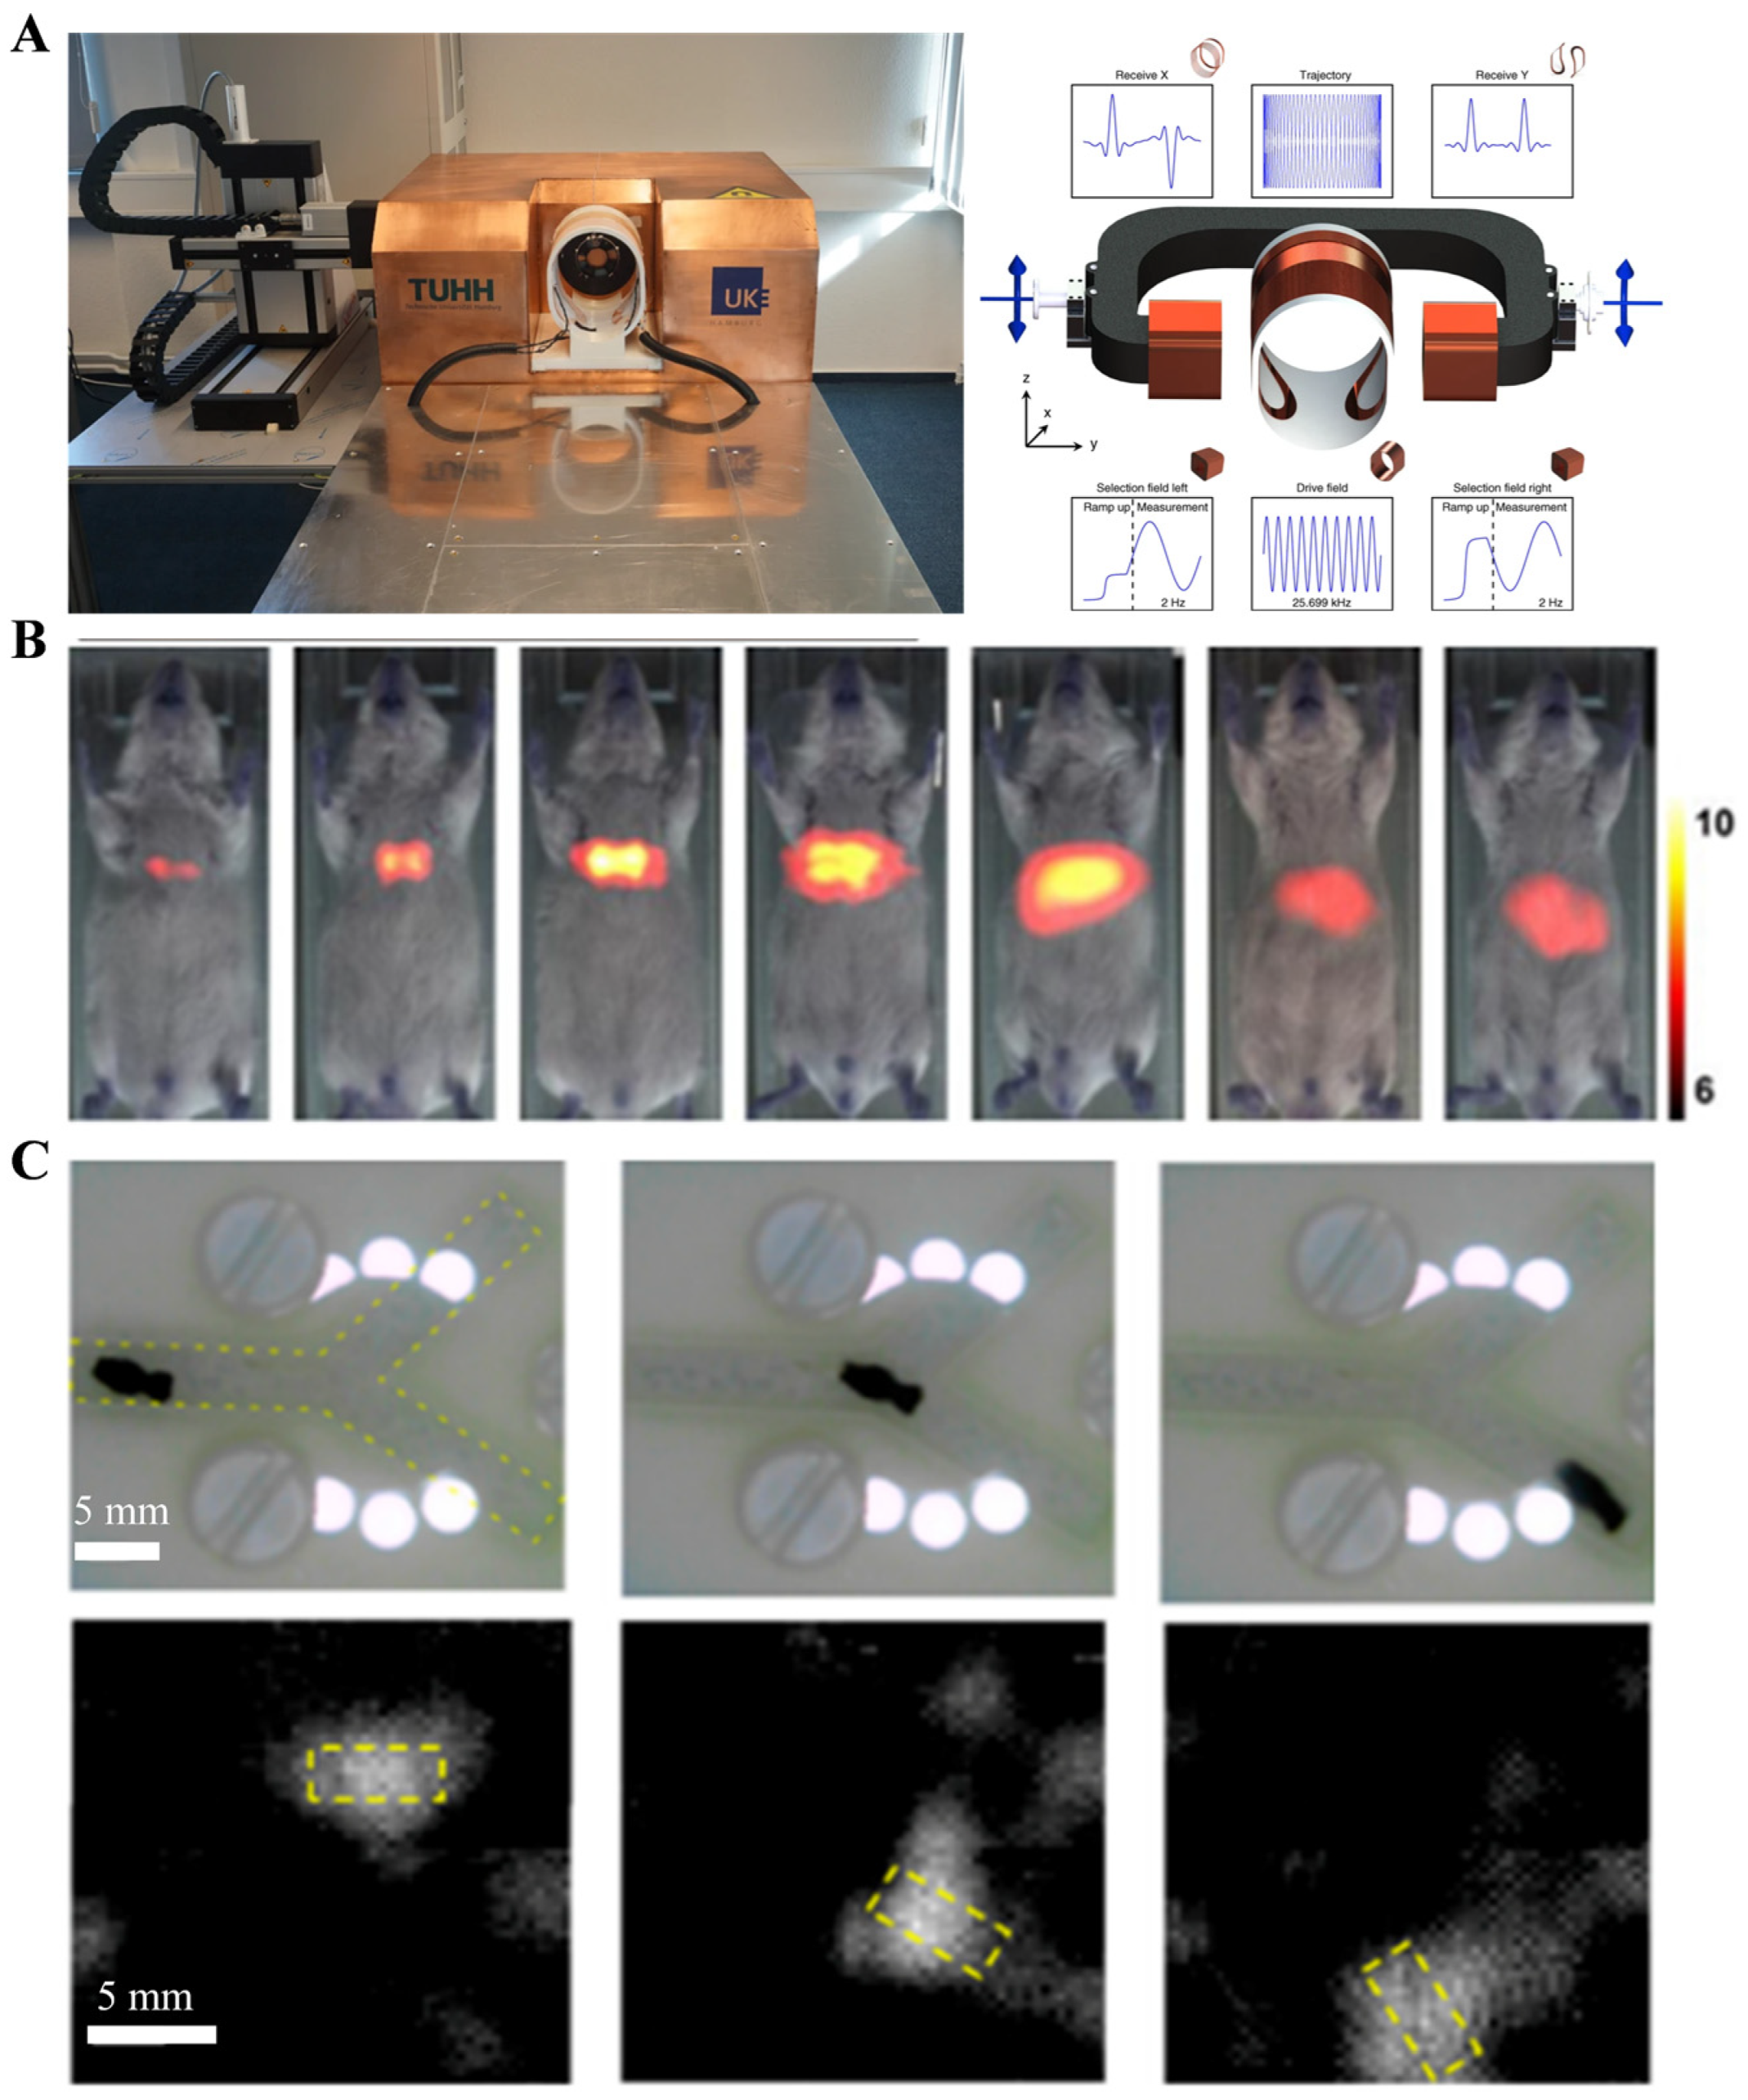

2.2.2. Magnetic Particle Imaging (MPI)

- Nothnagel, N.; Rahmer, J.; Gleich, B.; Halkola, A.; Buzug, T.M.; Borgert, J. Steering of magnetic devices with a magnetic particle imaging system. IEEE Trans. Biomed. Eng. 2016, 63, 2286–2293. [Google Scholar] [CrossRef]

- Gleich, B.; Weizenecker, J. Tomographic imaging using the nonlinear response of magnetic particles. Nature 2005, 435, 1214–1217. [Google Scholar] [CrossRef]

- Graeser, M.; Thieben, F.; Szwargulski, P.; Werner, F.; Gdaniec, N.; Boberg, M.; Griese, F.; Möddel, M.; Ludewig, P.; van de Ven, D.; et al. Human-sized magnetic particle imaging for brain applications. Nat. Commun. 2019, 10, 1936. [Google Scholar] [CrossRef]

- Han, X.; Li, Y.; Liu, W.; Chen, X.; Song, Z.; Wang, X.; Deng, Y.; Tang, X.; Jiang, Z. The applications of magnetic particle imaging: From cell to body. Diagnostics 2020, 10, 800. [Google Scholar] [CrossRef]

- Bakenecker, A.C.; von Gladiss, A.; Friedrich, T.; Heinen, U.; Lehr, H.; Ludtke-Buzug, K.; Buzug, T.M. Actuation and visualization of a magnetically coated swimmer with magnetic particle imaging. J. Magn. Magn. Mater. 2019, 473, 495–500. [Google Scholar] [CrossRef]